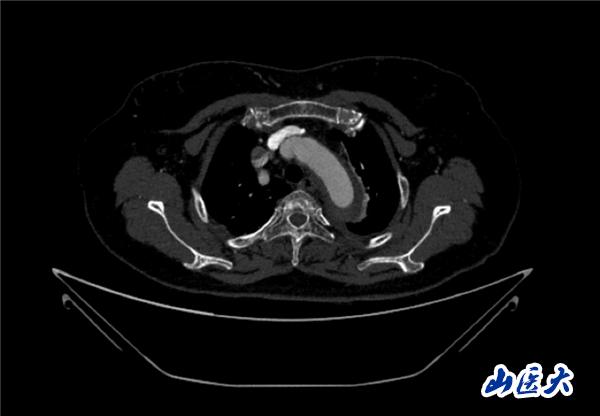

首例患者是一位55岁的女性,她患有高血压约2年时间,平时也会规律服用多种降压药,但血压控制始终不尽人意。2023年4月下午,她出现不明原因的头痛,在家拔罐缓解少许便未到医院就医,次日凌晨突感胸闷、胸背疼痛伴有呼吸困难等症状、家人急忙拨打了120,把患者送入医院急诊科进行救治,医生在急诊科行胸腹主动脉CTA时,显示主动脉弓部-降主动脉及腹主动脉壁间血肿,遂收治入医院血管外科,患者入院10天后复查血肿仍未有改善,依然伴有胸背部疼痛等不适,如不进一步处理,可能发展为夹层危及生命,患者及家属经过与医生团队了解沟通,决定进行创伤小、恢复快的介入手术治疗。张玮教授、符伟国教授、董红霖教授及其血管外科团队(闫盛、常文凯、田琴琴)共同商讨手术方案,最终确定使用Zipper™一体式主动脉弓覆膜支架系统,行胸主动脉覆膜支架腔内隔绝术+无名动脉、左颈总动脉、左锁骨下动脉分支重建术为患者进行治疗。董红霖教授及其血管外科团队根据患者术前头颅CT平扫提示双侧侧脑室旁缺血灶,血压控制不稳定,属夹层壁间血肿非典型夹层等风险点,制定了完整的手术方案,术中经股动脉置入Zipper支架主体,经预留导丝超选无名动脉,并确保主体支架对位准确,顺利置入左颈总动脉、左锁骨下动脉支架,重建弓上三分支。手术过程非常顺利。术后观察主动脉及分支覆膜支架定位准确;无内漏;分支支架通畅,动脉供血正常。

术前CTA